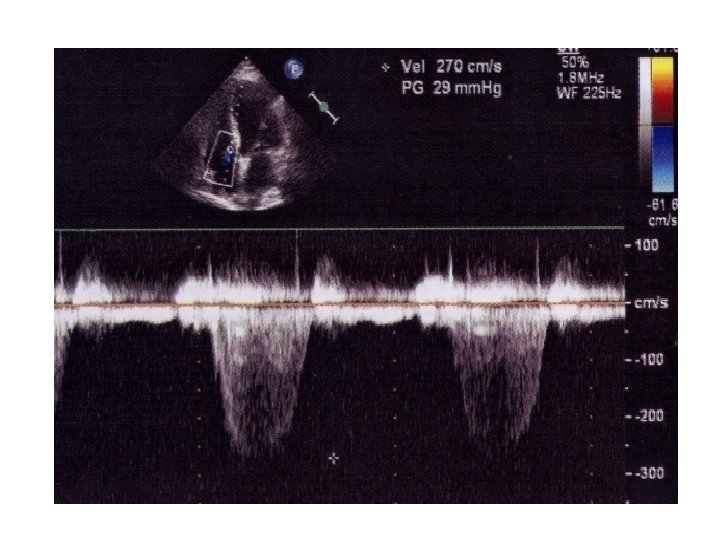

Continuous Wave Doppler • • • older and electronically more simple continuous generation of ultrasound waves continuous ultrasound reception two crystal transducer Blood flow along entire beam is observed

• ADVANTAGE ability to measure high blood velocities accurately • DISADVANTAGE 1)lack of selectivity or depth discrimination 2)no provision for range gating to allow selective placing of a given Doppler sample volume in space

Aliasing • The aliasing phenomenon occurs when the velocity exceeds the rate at which the pulsed wave system can record it properly Fig. 1. 24

Aliasing is represented on the spectral trace as a cut-off of a given velocity with placement of the cut section in the opposite channel or reverse flow direction